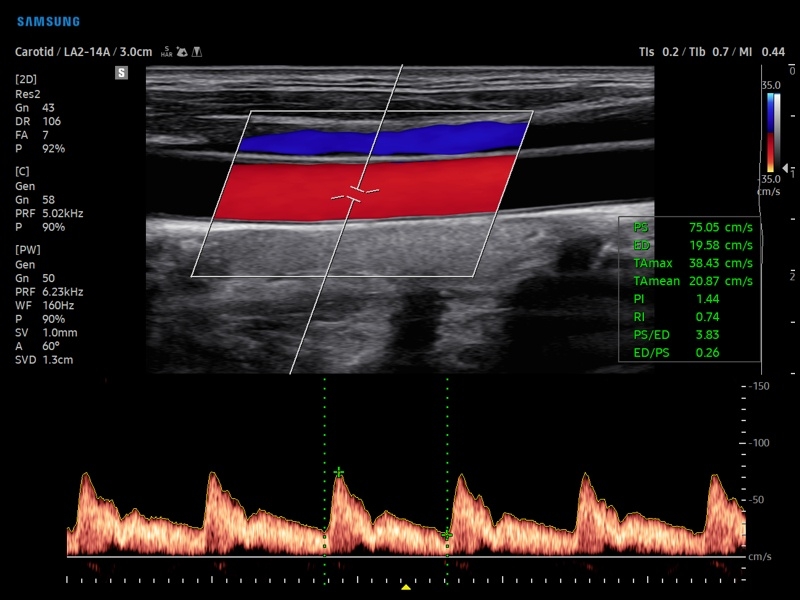

• Модуль AutoIMT - автоматическое вычисление комплекса интима-медиа общей сонной артерии (Intima Media Thickness). Данная оценка имеет большое значение для ранней диагностики атеросклероза и оценки риска развития инсульта и инфаркта миокарда.

• Модуль 2D Arterial Analysis программа, позволяющая автоматически провести анализ толщины и эластичности стенок разных участков сонной артерии, с выведением результатов в графической форме в движении (кинопетле) аналогично программе Strain для эхокардиографии.

• Сонные артерии:автоматическая, полуавтоматическая, ручная трассировка доплеровского спектра; ПСС, КДС, %СтПлощ, %Ст Диам, площадь сосуда, диаметр сосуда, средняя толщина интимы, объемный кровоток.